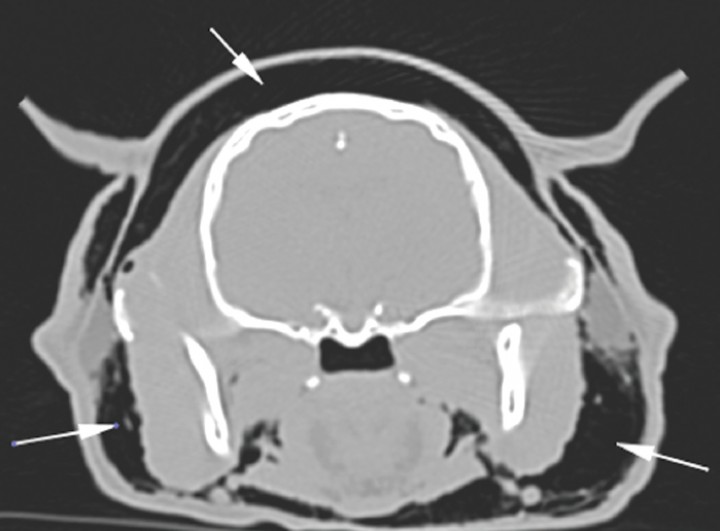

<p>Corte transversal a nivel de la cabeza en ventana hueso. Las fechas blancas señalan enfisema subcutáneo.</p>

Figura 5

Corte transversal a nivel de la cabeza en ventana hueso. Las fechas blancas señalan enfisema subcutáneo.

Para llegar a un diagnóstico definitivo podrían ser útiles una tomografía computarizada (TC) o una traqueobroncoscopia. En este caso debido a la historia clínica del paciente se decide hacer una TC. El estudio incluye dos series precontraste procesadas con algoritmos de tejido blando y pulmón, con cortes contiguos de 1 mm de grosor. Se observa dilatación marcada del mediastino con gas, o neumomediastino (Fig. 3), así como neumotórax y compresión de lóbulos pulmonares con atelectasia secundaria. El gas del mediastino se extiende a lo largo de los planos fasciales de los tejidos subcutáneos, causando enfisema muy marcado en cabeza, cuello, pared torácica y pared abdominal. El aire también se extiende caudalmente al espacio retroperitoneal (Fig. 4), cabeza (Fig. 5) y cuello (Fig. 6). Se detecta un pequeño defecto en la pared dorsal de la tráquea, aproximadamente a nivel de C7-T1 (Fig. 6B). Se observa mineralización a nivel del riñón derecho.